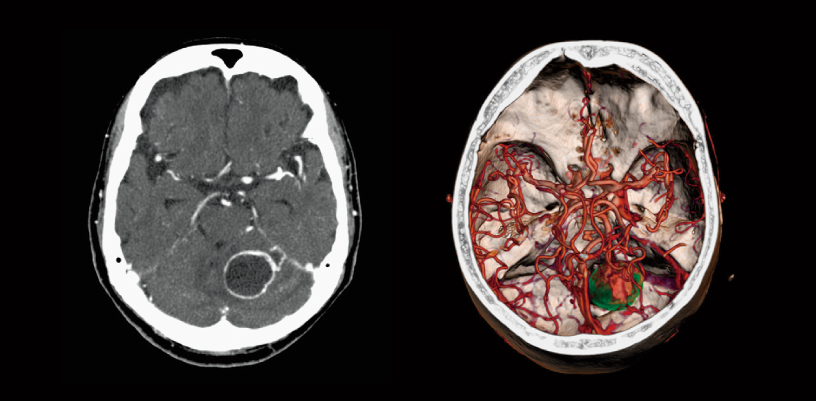

FBP(izquierda)

Intelli IPV(derecha)

Tumor cerebral